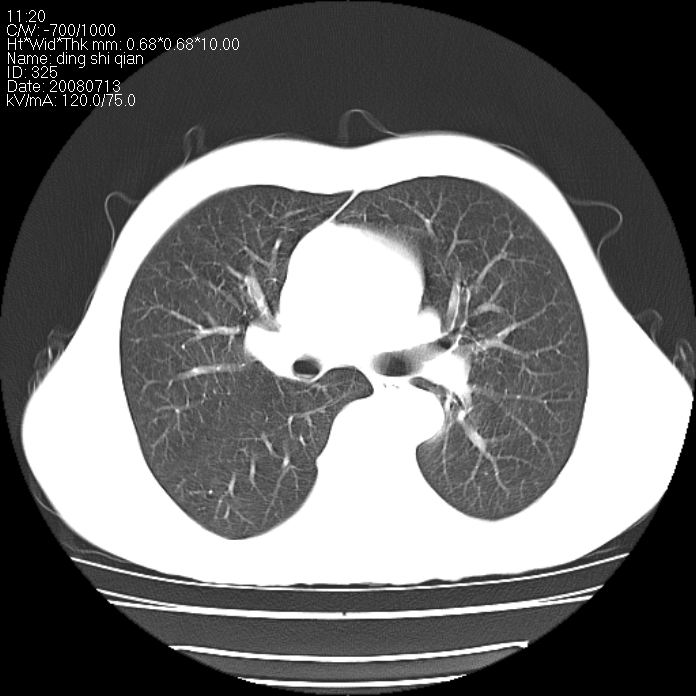

标题: CT14654:男 50岁 近来胸痛 [打印本页]

标题: CT14654:男 50岁 近来胸痛

右侧上肺块状软组织影,浅分叶,边缘毛刺证,与胸膜粘连,考虑:周围性肺癌

右肺上叶周围型肺癌可能性大。

典型右肺周围型肺癌

右肺上叶周围型肺癌可能性大